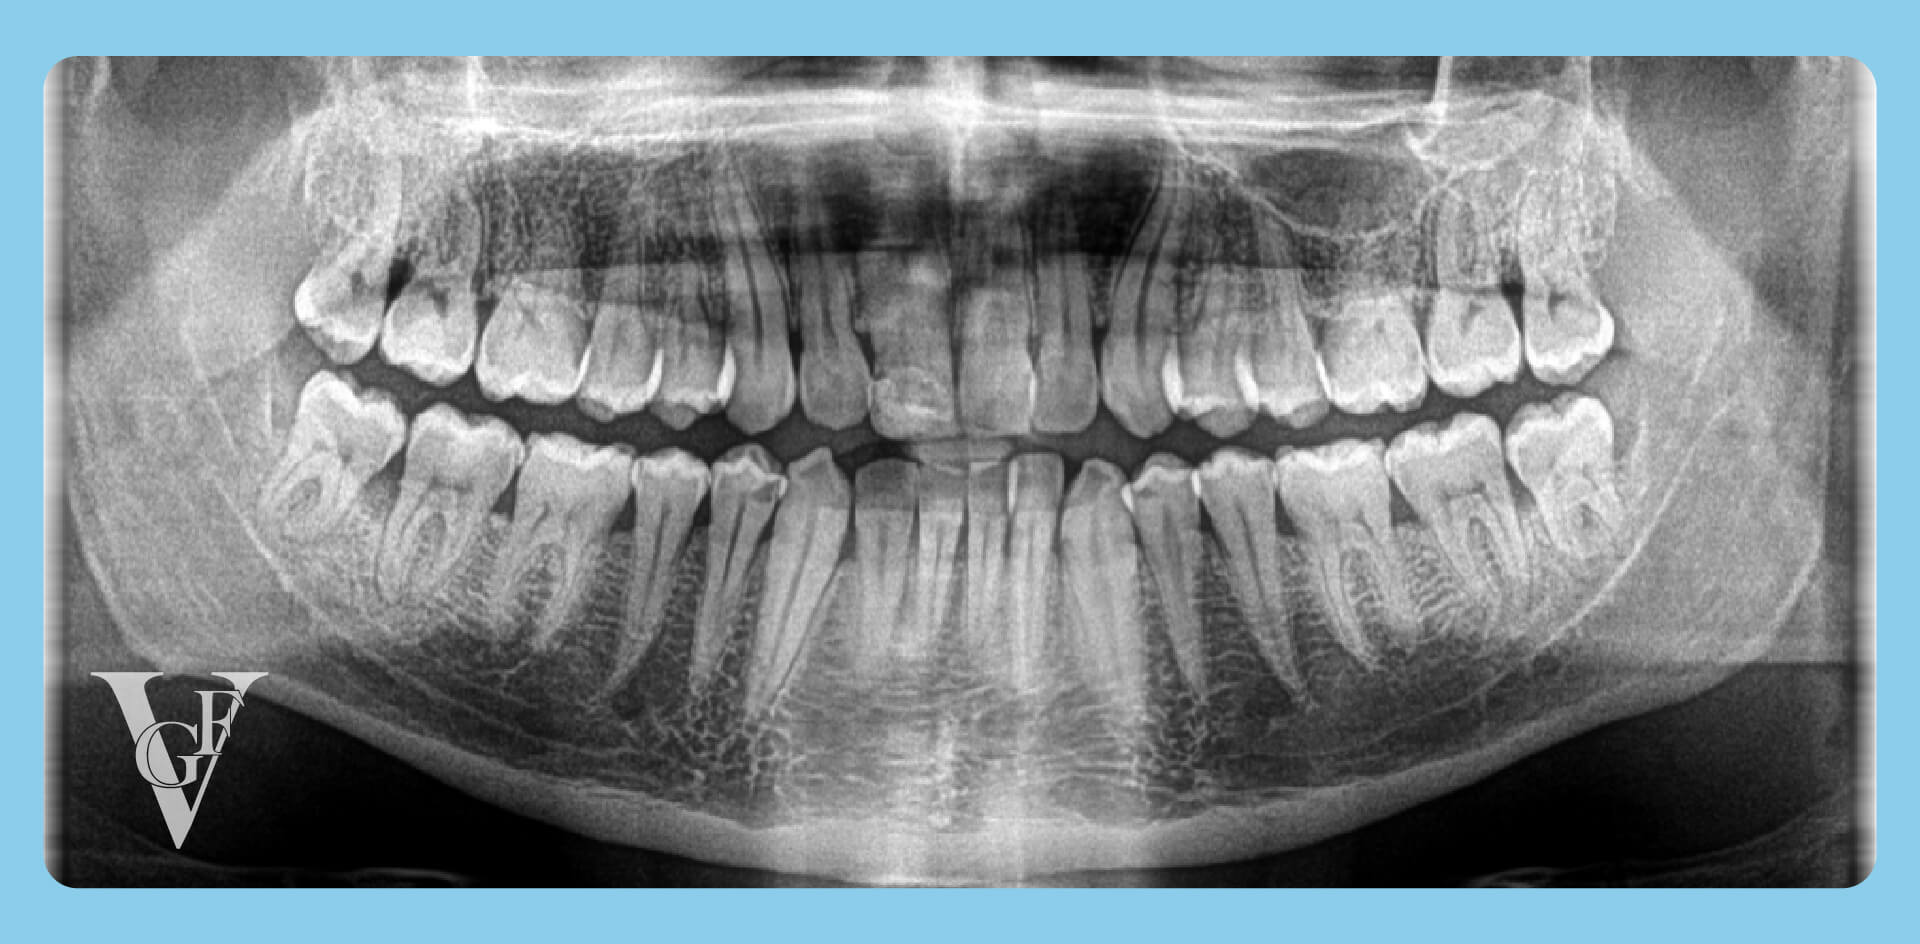

Per seguire il processo di crescita e valutare le condizioni dei denti del giudizio, è possibile utilizzare una radiografia panoramica.

Tutto comincia con il germe, una struttura embrionale iniziale del dente. Intorno ai 13, 14 anni possiamo trovarci proprio in questa fase con un accenno di corona dentale ma senza radice.

In condizioni normali di spazio adeguato, la corona che è già abbozzata continua lentamente a crescere. Con il passare del tempo, anche la radice diventa sempre più pronunciata. Questo processo continua fino a quando il dente non è completamente posizionato nell’arcata dentale.

Quando un dente non riesce a erompere e si blocca a metà strada, può trovarsi in una posizione irregolare oppure, per mancanza di spazio, scontrarsi con il settimo dente (secondo molare). A seconda dell’inclinazione, il dente può restare parzialmente o totalmente incluso.